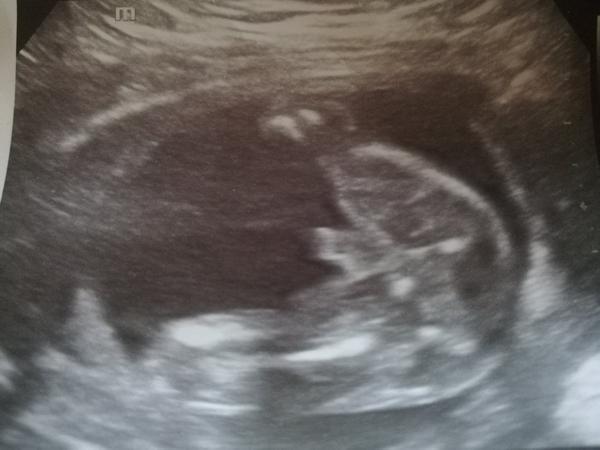

tak já se předevčírem dozvěděla, že čekáme chlapečka a to jsem ve 38. týdnu, za 14 mám jít rodit...doma 70% věcí růžových, protože mi doktorka tvrdila v 5. a 6. měsíci, že je to děvče. Už jsem rodině ani přátelům nic neříkala, ještě se s tím sama srovnávám :D no a vymýšlíme jméno pro chlapce.... i když mám obrázek z ultrazvuku a na něm jasný varlátka a pindík, čekám co z toho nakonec vyjde.... 🙂

@looolaaa to už je chlap..pindík zretelnej

@lujda661 podle utz to na kluka opravdu vypadá..

@lujda661 jasný kluk, máme stejnou fotku z utz v 16tt a je to kluk 😀